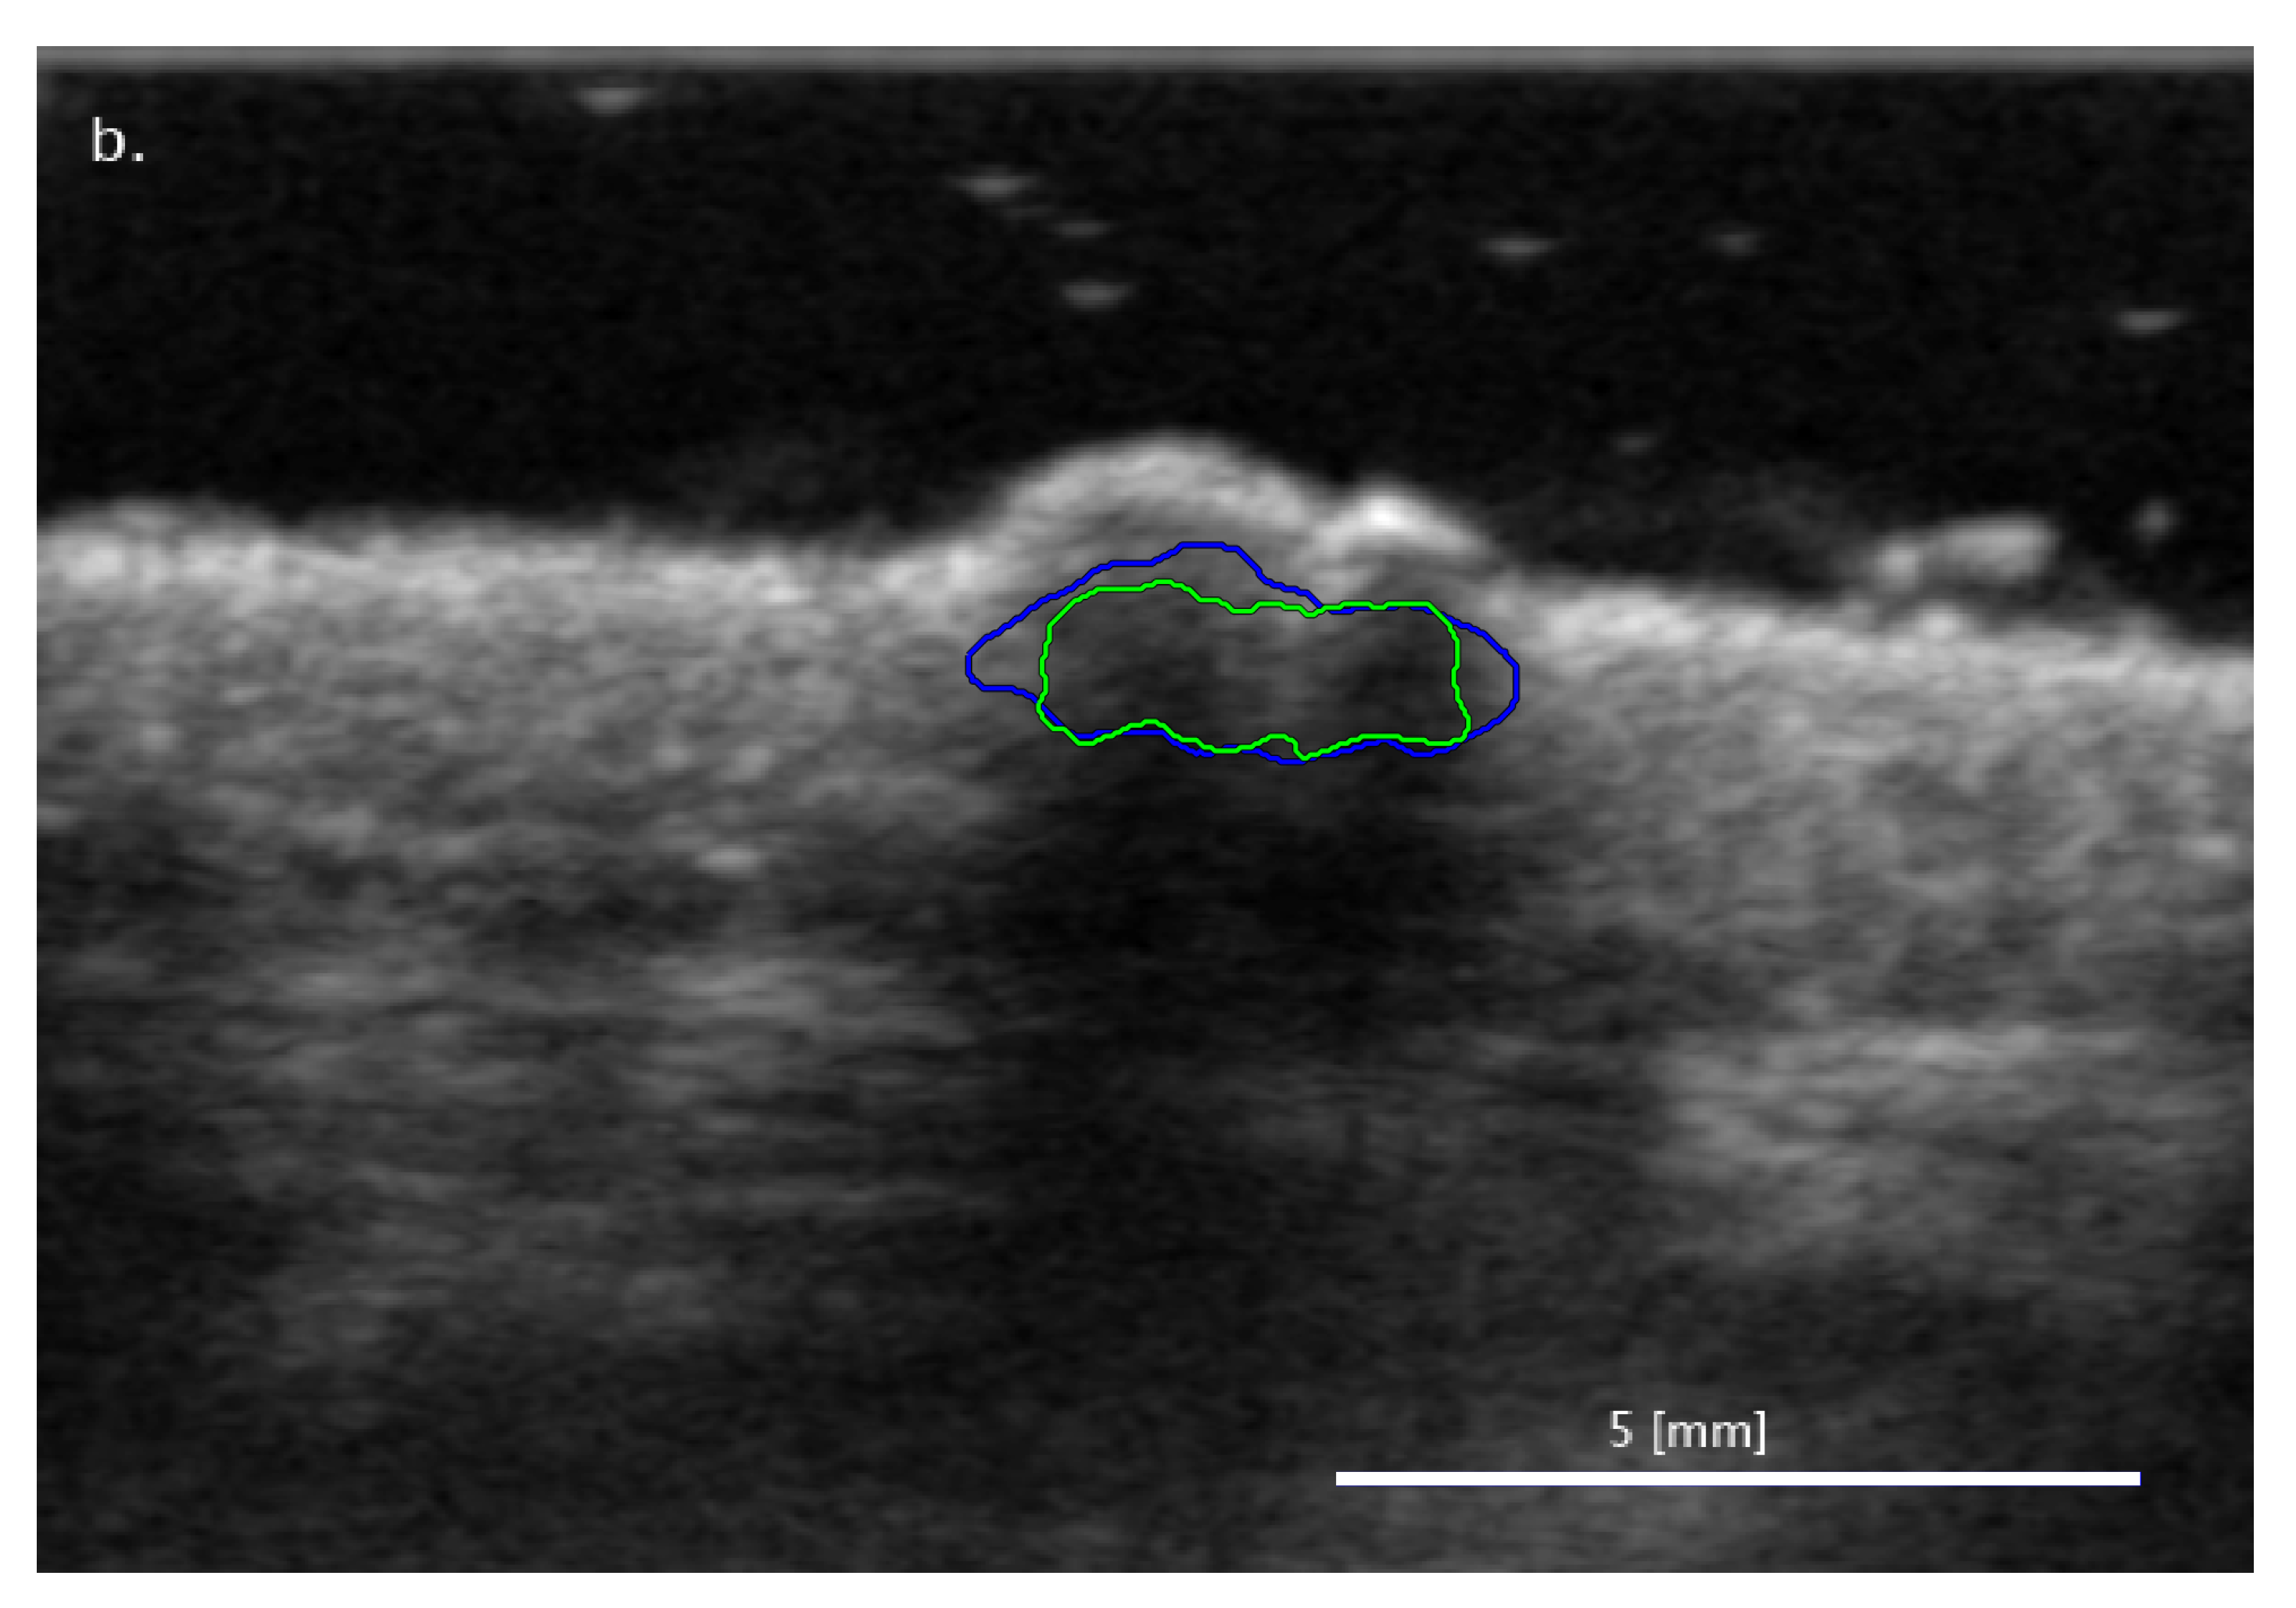

3.2. Comparison of FA and SA Classification Performance with Representative Images

3.2.1. Cases When FA Fails While SA Methods Perform Correctly

3.2.2. Cases When the Two SA Methods Return Different Classifications

3.2.3. Cases When the SA Methods Both Fail While the FA Method Performs Correctly

3.3. Sensitivity of Classification to Changes in Lesion Segmentation